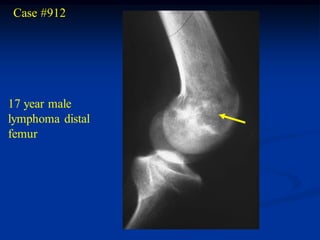

Case #912

17 year male

lymphoma distal

femur

AP view

Coronal T-1 MRI

tumor

Sagittal T-1 MRI

Case #913               Coronal T-1 MRI